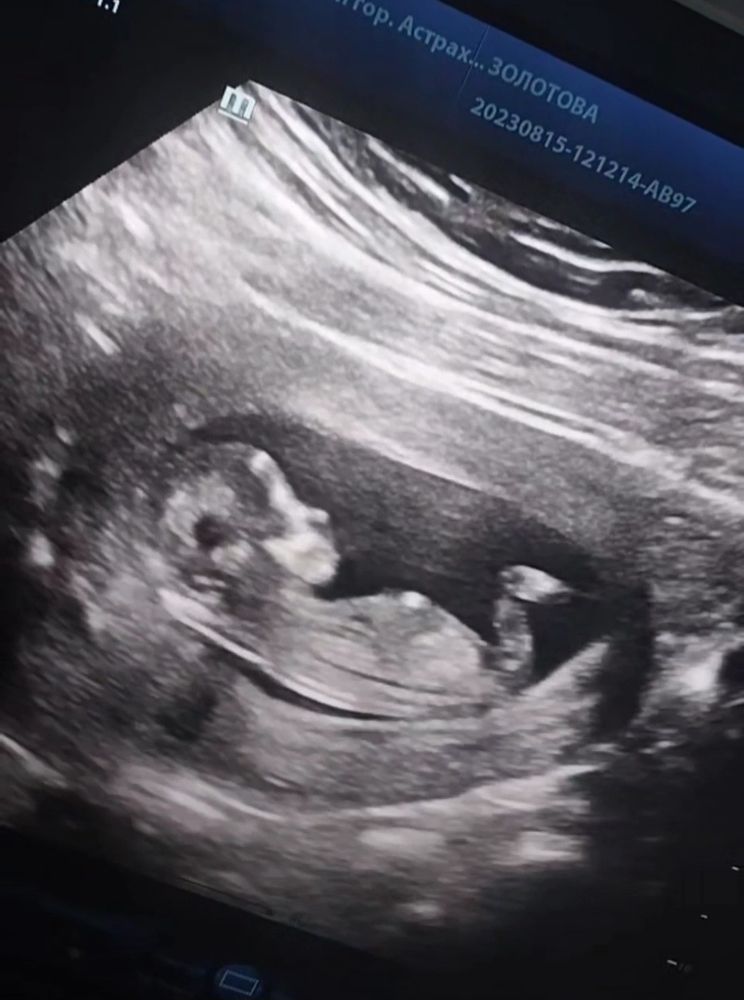

Викки в Благополучная беременность 2 года На память 🥰😘💕🤰 12+5, 15.08.2023 первый скрининг ❤️6,1см, сб 158 !😍😍😍 Посмотрите еще 20 записей на эту тему Лучший ответ Lelya Хорошенький 💕 05.09.2023 Ответить Викки Lelya, как у вас дела? 05.09.2023 Ответить Lelya Викки , все хорошо, тоже растём. Скрининг 2 недели назад прошла. Теперь жду приём врача и должны назначить цервикометрию и второй скрининг 06.09.2023 Ответить Отменить Ответить Александра 🥰💞 06.09.2023 Ответить Лиса Какая красота😍😍😍 05.09.2023 Ответить Викки Лиса, ты как, дома?? 05.09.2023 Ответить Лиса Викки , да, дома. Хорошо что сейчас в отпуске 05.09.2023 Ответить Ясенька Какой милый профиль❤️🥰есть предположения кто в домике ? 05.09.2023 Ответить Викки Ясенька, есть)) но я не хочу смотреть до определённого срока 05.09.2023 Ответить Ясенька Викки , 🥰 05.09.2023 Ответить 3 раз как в 1 раз 😁 Анализ мочи, вопрос Чаты Беременных Выберите чат: Январята-2026 Февралята-2026 Мартята-2026 Апрелята-2026 Майчата-2026 Июнята-2026 Июлята-2026 Августята-2026